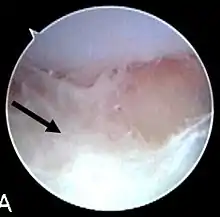

Septic arthritis as seen during arthroscopy[1] The arrow points to debris in the joint space. | |